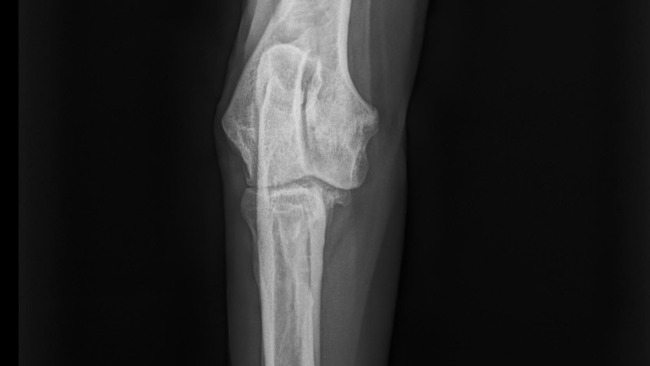

Zdjęcia RTG - łokieć po artroskopii i kość łokciowa do zabiegu osteotomii.

Magnus jest po artroskopii łokcia, po której okazało się, że są wskazania do drugiego zabiegu chirurgicznego - osteotomia kości (PAUL osteotomy).

Zdania weterynarzy są podzielone. Dlatego zdecydowałam, że ostateczną decyzję podejmę po powtórzeniu badań i ponownym prześwietleniu i porównaniu wyników. Być może możliwe będzie inne, mniej inwazyjne leczenie, ale równie kosztowne i co ważne - powtarzalne.